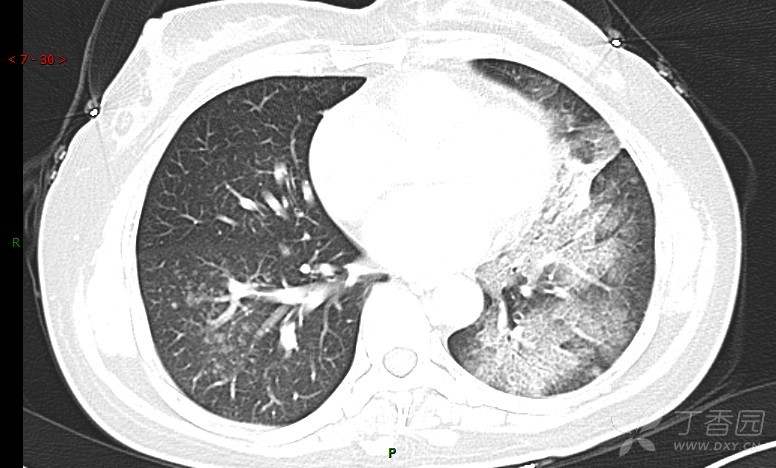

腺泡结节影,蜂窝征,这些都在提示……(病例3连发,附其他2例链接,病理已公布)

咳嗽1年余,加重7天。

患者于1年余前始受凉后出现咳嗽,多为干咳,未在意,未到医院就诊。近3月患者出现咳痰,多为黄色粘痰,量大,伴乏力,偶有头晕、心慌,无发热、胸痛、憋喘,无低热、盗汗、咯血、胸痛,无头痛,无恶心、呕吐、腹痛、腹泻,无尿频、尿急、尿痛,在当地诊所给予抗感染等对症支持治疗(具体药物及剂量不详),症状仍时有反复。患者于1月余前到外院就诊,行胸部CT提示双肺炎症,左肺重,考虑为“间质性肺炎”,给予“左氧氟沙星、利巴韦林、头孢哌酮舒巴坦钠注射液”治疗,复查胸部CT示病灶吸收不理想,后出院继续于诊所对症治疗(具体药物及剂量不详),效果欠佳。7天前患者无明显诱因出现上述症状加重,为求进一步诊治,特来我院就诊,我院门诊以“肺炎(重症)?”收入留观室,留观室给予“盐酸莫西沙星氯化钠”等对症治疗后,今日转入我科。患者自发病以来,神志清,精神差,饮食正常,睡眠增多,大小便正常,体重近3月减轻5公斤余。